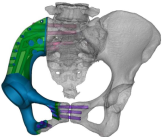

术前截骨规划

据主刀医师徐生林介绍,本例病例将整个右侧半骨盆Ⅰ+Ⅱ+Ⅲ+Ⅳ区(累及骶骨)进行整块切除,同时切除肿瘤覆盖的部分骶骨。3D打印假体所有骨接触界面均设计为骨整合结构,有利于骨长入和骨盆假体的永久稳定。耻、坐骨结构不规则,因此设计组配式结构,有利于术中操作,极大地方便了术中的假体安装。